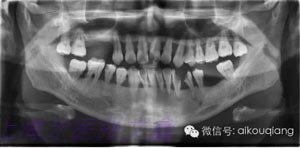

下面這張X光片是比較典型的牙周炎的X光片,該患者全口所有的牙齒都呈現(xiàn)出2~3度的松動(dòng)?;颊攥F(xiàn)在感覺無(wú)法用牙齒咀嚼。坦白地講,牙周炎發(fā)展到這種程度,很多時(shí)候醫(yī)生也束手無(wú)策了。為了保留更多的牙槽骨,醫(yī)生會(huì)不得不拔掉那些嚴(yán)重松動(dòng)的牙齒。